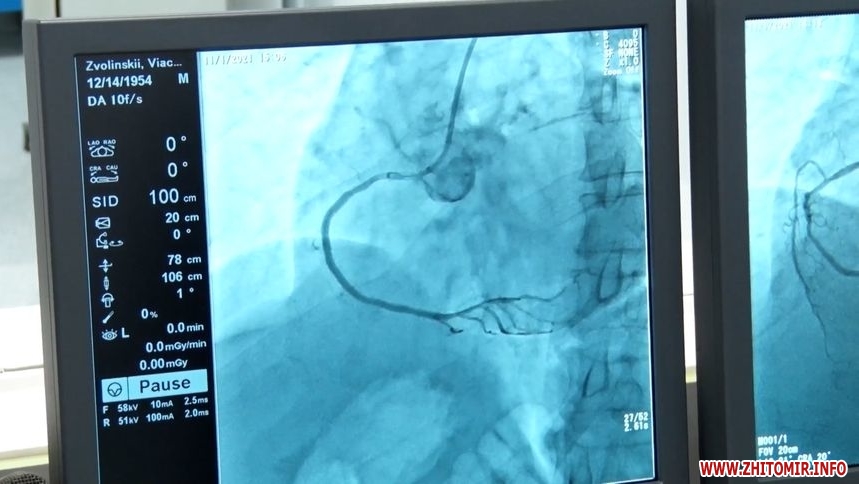

«Саме дозвіл лікарні на взяття кредиту до 57 млн грн, також виділено 10 млн грн з міського бюджету на перший внесок. З 2021 року у нас вже працює ангіограф у лікарні №2, він зараз завантажений практично 24/7. Виникла необхідність у придбанні другого ангіографа, тому що у 2023 році ми відкрили нейрохірургічне відділення, яке потребує такого обладнання. До місяця у нас є черга, якщо потрібно пройти планове обстеження. Бо інколи виникають такі ситуація, як декілька тижнів тому: у нас була дитина 15 років, якій була надана нейрохірургічна допомога за допомоги ангіографа і дитина врятована», – говорить заступниця Житомирського міського голови Марія Місюрова.

Нагадаємо, на позачерговій сесії Житомирської міської ради 20 лютого 2020 року виділили 13,46 млн грн з міського бюджету для співфінансування купівлі у лізинг ангіографа, який функціонуватиме на базі КП «Лікарні №2 ім. В. П.Павлусенка». З 25 жовтня 2021 року нове обладнання почали використовувати для діагностики та лікування, зокрема, за тиждень в лікарні №2 провели 14 коронарографій і 3 стентування.